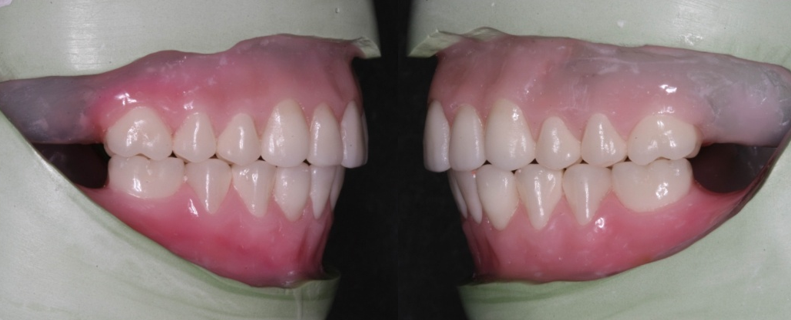

After years of wear, older forms of dentures can become uneven and uncomfortable. If your dentures are moving around in your mouth or are painful to use, you should have them replaced.

At Dental Innovations in Wasilla, AK, we can fit the very latest implant supported dentures, implant retained dentures, or more complex or targeted solutions for a particular patient situation. Contact our team today to arrange a consultation.